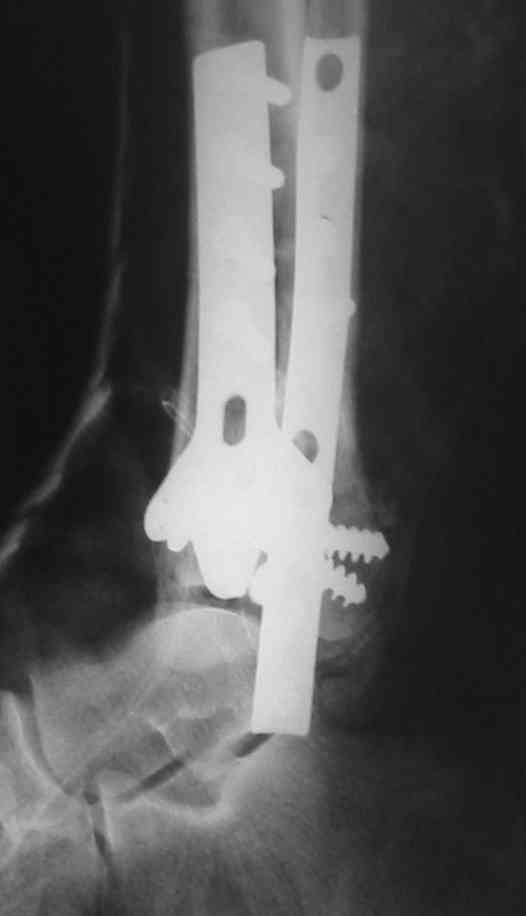

Посылаю результат лечения предыдущего больного через год.

С уважением Дрягин

Кстати, при переломах переднего края по классификации АО В-3 при переломах пилона пластина укладывается по передней поверхности. Она достаточно тонкая и эластичная, не надо этого бояться. Посылаю три снимка.